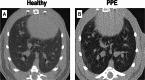

Acute respiratory distress syndrome (ARDS), chronic obstructive pulmonary disease (COPD), and pulmonary fibrosis are major respiratory conditions associated with significant morbidity and, in some cases, high mortality. A variety of animals models have been established to study these disorders, primarily focusing on histologic alterations, cellular signalling pathways, inflammatory responses, lung perfusion, gas-exchange abnormalities, and response to emerging therapies. Imaging techniques play a crucial role in these investigations, enabling in vivo assessment of lung structure and function. The most widely used imaging modalities include computed tomography (CT), positron emission tomography (PET), and electrical impedance tomography (EIT). While CT and, to a variable extent, PET involve ionizing radiation, EIT is a radiation-free technique. Despite anatomical differences between species, many imaging and physiological findings observed in animal models are consistent with those seen in critically ill patients, enhancing their translational relevance. This narrative review provides a comprehensive overview of the applicability of these imaging techniques in animal models and explores their relevance to human pathophysiology and clinical management.